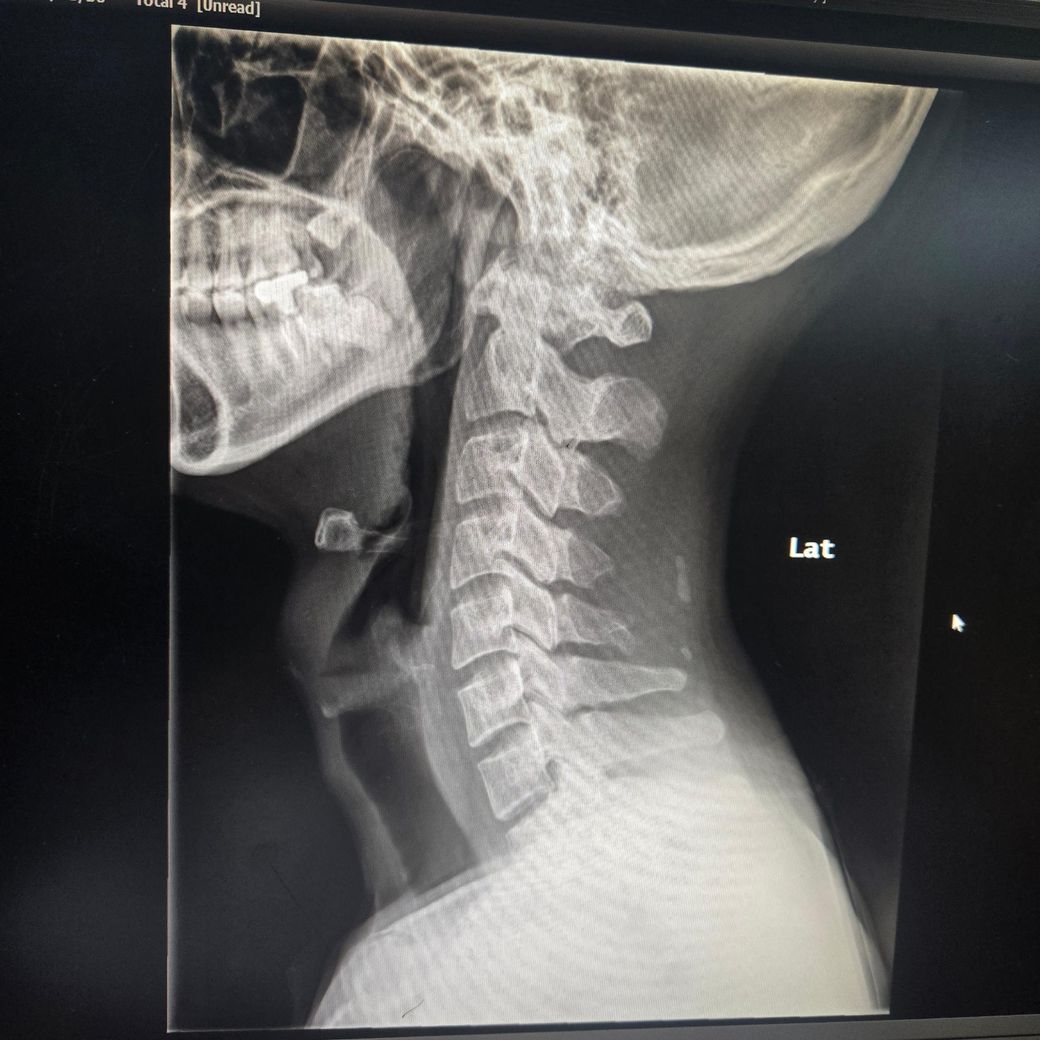

3달째 어지럼증과 경추1,2번쪽과 후두가 베개에 눌리거나 고개를 굽히면 눈도 울렁거리고 맥박도 느껴져요Xray사진인데 경추불안정증이 있나요? 부탁드립니다..경추mri 뇌mri mra 귀 눈 검사는 다 해봤지만 정상입니다.심리쪽 약도 먹었지만 변동없습니다.목 뻐근함과 같이 어지럼증이 왔습니다. 자고일어난후

경추불안정성의 경우 환자분의 경우 C1, C2 사이 거리 혹은 각도를 측정을 해야 합니다.

엑스레이 사진상 flexion과 extension에서 차이는 나지만 그것을 정량적으로 측정을 하기 위해서는

실제 엑스레이 사진으로 평가를 해야 합니다.